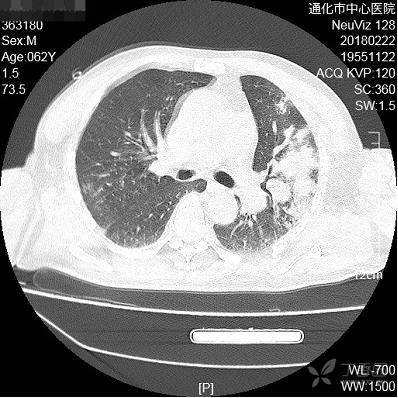

男,62岁。一氧化碳中毒昏迷而冻伤,因发现急性肾功能衰竭入住肾内科,入院后发现寒战发热、咳嗽、咯粘稠黄痰。嗜酒:2两/日,吸烟:3-5支/日。无糖尿病。

血常规白细胞1.2万。

治疗:头孢哌酮舒巴坦静点

考虑什么细菌感染?